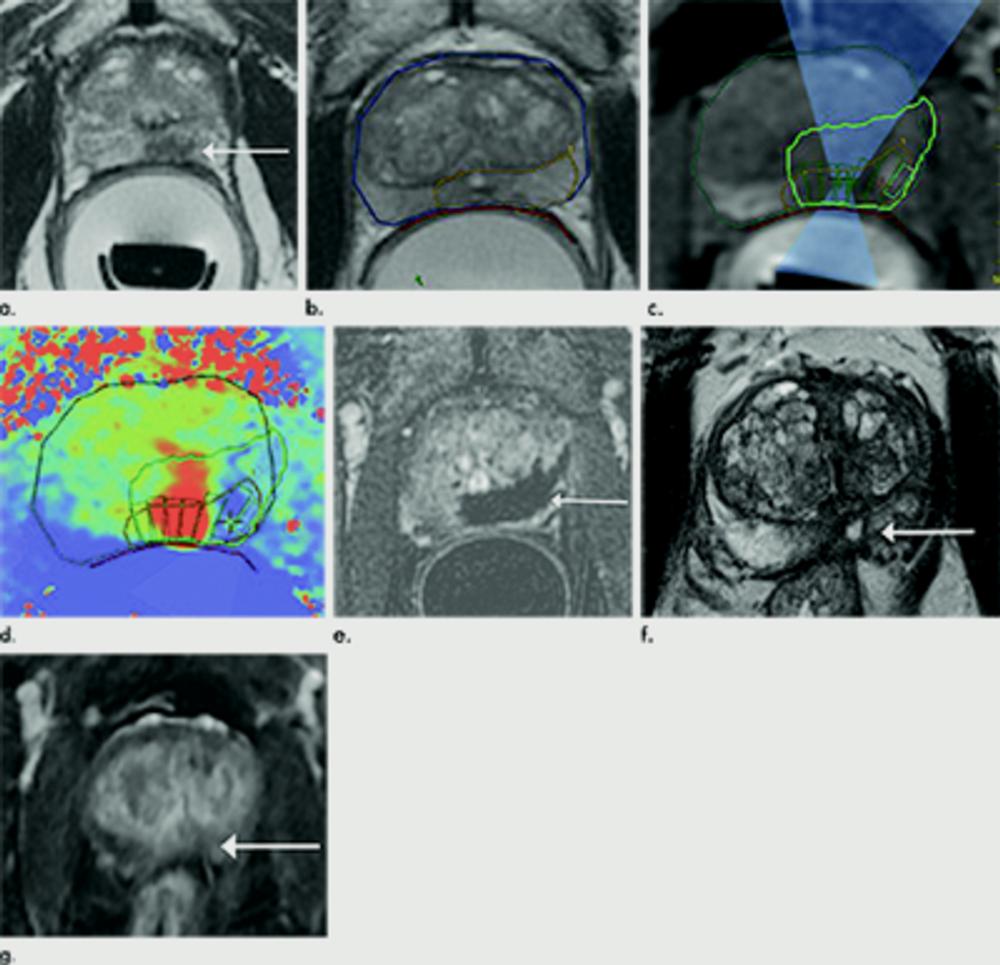

Figure 1. Images in 69-year-old man with biopsy-confirmed Gleason score 7 (3+4) prostate cancer. (a) Pretreatment axial T2-weighted fast spin-echo MRI scan (repetition time msec/echo time msec, 3820/97) shows tumor in midline anterior transition zone (arrow). (b) Intraoperative MRI scan shows contoured rectal wall (red line), prostate margin (blue outline), and region of interest (orange outline). Because the urethra was included in planned treatment volume, a suprapubic catheter was placed for continuous bladder drainage during treatment. (c) Intraoperative MRI scan shows focused ultrasound beam path (blue) overlaid on treatment plan. Rectangles illustrate each sonication spot. (d) Thermal map image obtained during treatment with heat deposition color coded in red overlaid on sonication spot. (e) Axial gadopentetate dimeglumine–enhanced MRI scan (230/2.97) obtained immediately after treatment shows devascularized ablated volume (arrows). (f) Corresponding T2-weighted fast spin-echo MRI scan (3820/97) at 5 months after ablation shows complete involution of transition zone. All seven cores from treatment area margins were negative for cancer at biopsy.